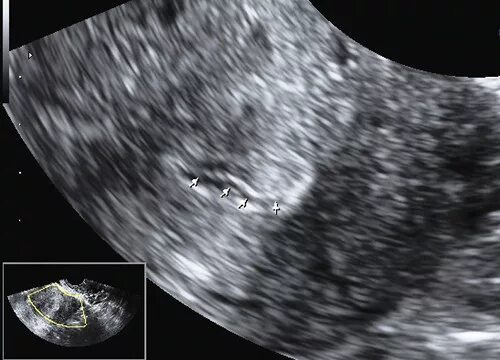

Серозометры в матке что это такое